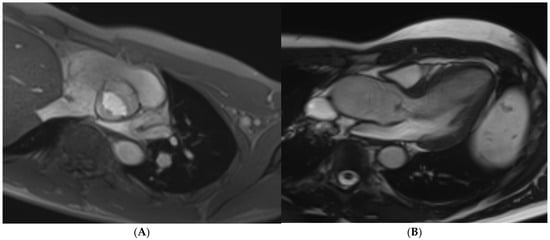

Cardiac MRI protocols in athletic individuals are quite similar to the ones employed for sedentary individuals (Figure 1). Appropriate sequences should be pre-determined according to the clinical indication. Most cardiac MRI protocols will consist of full body scouts, Steady-State Free Precession (SSFP) cine imaging (3 long-axis views and a short-axis stack), phase-contrast flow imaging, parametric mapping, and post-contrast imaging. Different sequences will answer different questions. Scouts are useful to image the great vessels and to evaluate extracardiac shunts in surgically repaired congenital heart disease patients. Cine imaging is required for LV/RV volumetric assessment, EF quantification, and LV/RV wall thickness. Phase contrast is needed to assess valve function and shunt quantification. Mapping sequences are required to rule out interstitial fibrosis, myocardial oedema, and injury. Pre-contrast and post-contrast T1 mapping is required to calculate extracellular volume. Post-gadolinium imaging is required to visualise the extent and pattern of replacement fibrosis [19].

Figure 1. Commonly adopted cardiac MRI sequences when evaluating athletes.

Other dedicated sequences will depend on the clinical indication for the cardiac MRI scan. T2-weighted oedema imaging and T2 mapping a must if there is a suspicion of myocarditis. An axial cine stack of the RV may be required to rule out regional wall motion abnormalities of the RV free wall, with or without fat suppression if there is a suspicion of ARVC or fatty infiltration. A more extended axial cine stack should be considered if anomalous pulmonary venous drainage is suspected. Ischaemia testing (perfusion) with adenosine or regadenoson should be considered if an athlete presents with chest pain in the context of a structurally normal heart or epicardial stenosis. Perfusion imaging is also reasonable when microvascular dysfunction is suspected in athletes with hypertrophic cardiomyopathy (HCM). Tagging sequences to evaluate myocardial deformation are also reasonable in athletes with a suspicion of HCM CMR-feature tracking (CMR-FT) also provides a valuable insight into diseases’ severity and progression, with evidence of subclinical LV and left atrial dysfunction present in a significant proportion of HCM patients with a normal LV EF [28,29]. Early acquisition after gadolinium administration (within 1–2 min) may be required if extensive areas of akinesia raise suspicion of an intracardiac thrombus. Three-dimensional (3D) angiography is useful when there is suspicion of aortic dilatation, aneurysms, or aortic coarctation [19]. The various sequences at the imager’s disposal only serve to improve the diagnostic quality of the scan. Adapting these sequences to the clinical question is paramount for a more personalised treatment pathway.